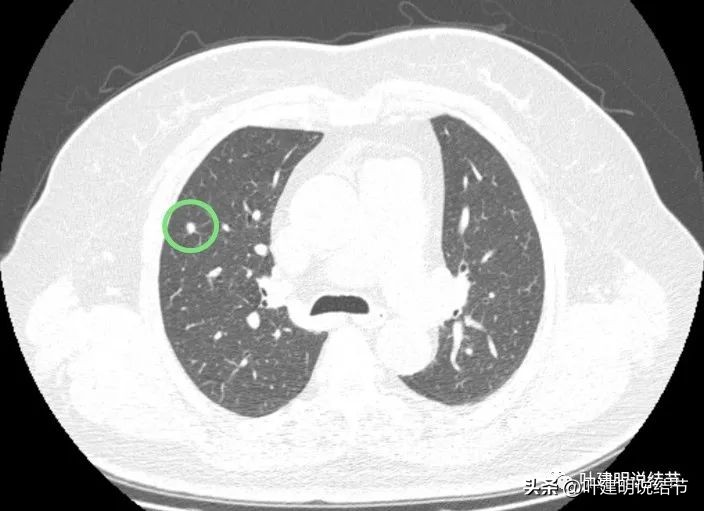

病灶2:右中叶微小实性结节,考虑纤维增生结节可能性大